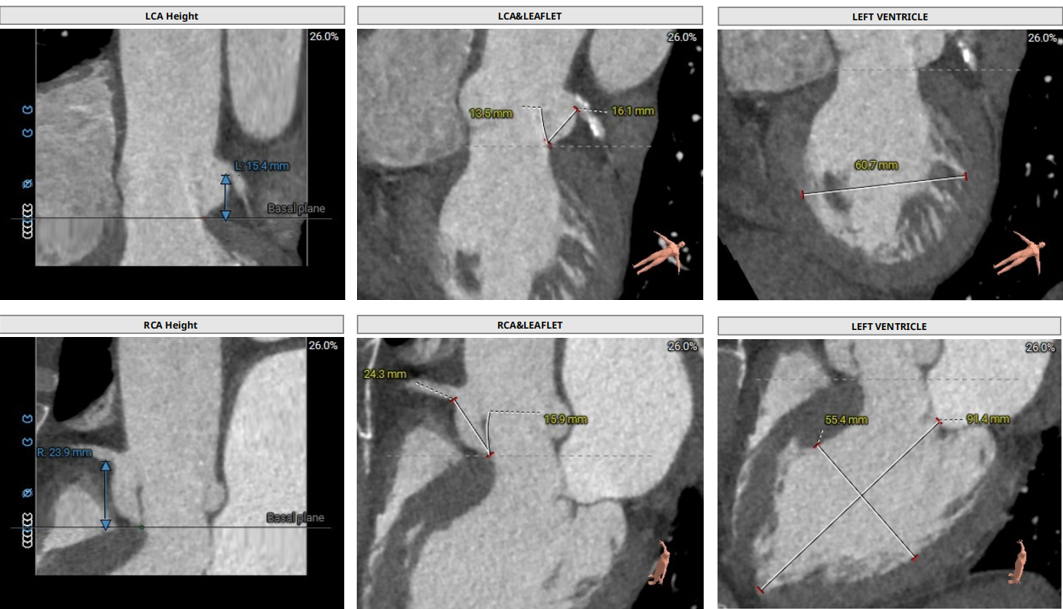

术前CT评估:

• Type1型二叶式主动脉瓣,R-N窦钙化融合嵴,瓣叶重度钙化伴增厚,L-N窦局部粘连。

• 冠脉开口高度可,左冠瓣叶稍冗长,左冠切线位瓣叶长度>冠脉开口到瓣叶附着缘距离,右冠切线位瓣叶长度<冠脉开口到瓣叶附着缘距离。

• 瓦氏窦、窦管交界内径可,升主动脉扩张,左室腔内径增大。

• 瓣环水平夹角46° ,主动脉弓宽度、角度尚可。

主动脉根部测量

冠脉阻挡风险评估

• 三叶式主动脉瓣,瓣叶轻微增厚,流出道呈敞口形态。

• 冠脉开口高度可,左右冠切线位瓣叶长度<冠脉开口到瓣叶附着缘距离。

• 瓦氏窦内径偏大、窦管交界,升主动脉内径可,左室腔内径正常。

• 瓣环水平夹角61° ,主动脉弓宽度、角度尚可。